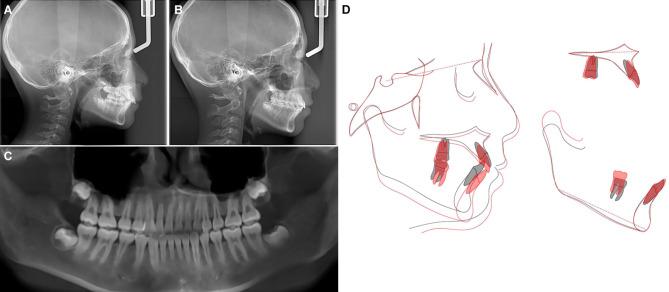

CASE PRESENTATION

An 11-year-old girl was diagnosed with Class II division 1 malocclusion and impaction of the maxillary right lateral incisor caused by an odontoma. A non-extraction treatment plan was implemented, involving first the distalization of the maxillary molars and utilization of the leeway space to create an eruption space, followed by surgical exposure and orthodontic traction, and finally, anterior teeth retraction and mandibular advancement guided by Class II elastics. After 39 months, the impacted maxillary right lateral incisor was successfully aligned, achieving Class I molar and canine relationship with a normal overbite and overjet and an improved facial profile.

病例报告

一名11岁女孩被诊断为安氏II类1分类错牙合,上颌右侧侧切牙因牙瘤而埋伏阻生。实施了不拔牙治疗方案,首先进行上颌磨牙远移并利用替牙间隙创造萌出间隙,随后进行外科开窗和正畸牵引,最后,使用II类牵引引导前牙内收和下颌前伸。39个月后,上颌右侧埋伏阻生侧切牙成功排齐,达到磨牙和尖牙I类关系,覆盖和覆牙合正常,面部轮廓得到改善。